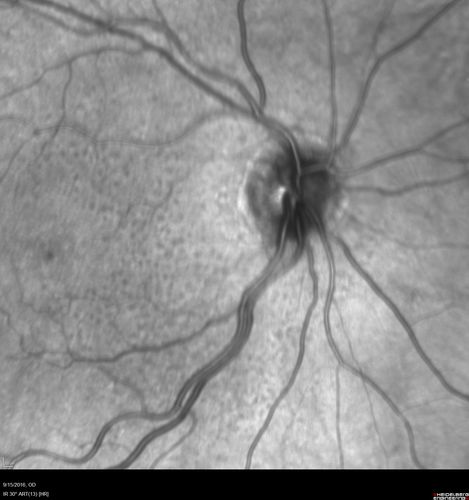

Perifoveal Microaneurysm - Not Diabetic (also reticular pseudodrusen)

87 year old female with fluctuating macular edema in the right eye from a perifoveal MA. (no treatment). VA 20/40 OU